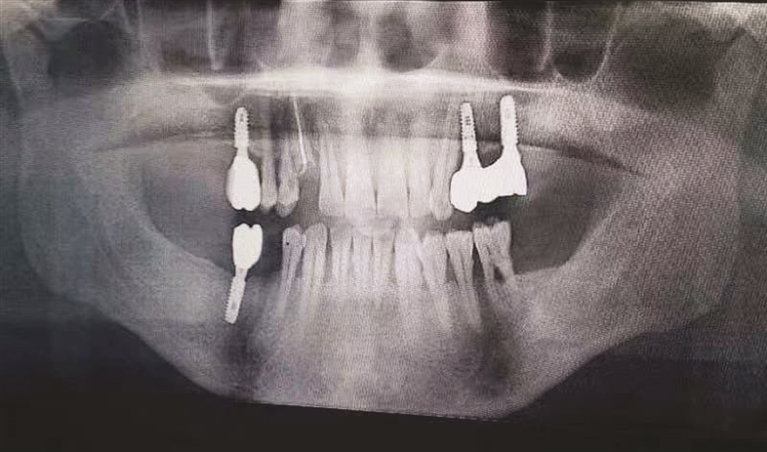

由市口腔医院供图